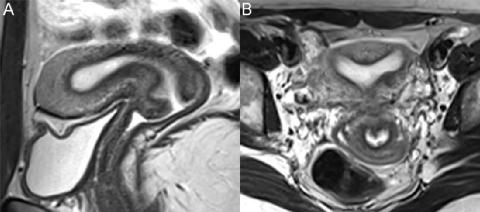

胚胎学上,两个苗勒管融合形成上阴道、子宫颈、子宫和输卵管。由该融合产生的囊肿在MR表现上相似,并根据位置命名:子宫颈内的Nabothian囊肿、盆腔横膈膜下后外侧外阴阴道前庭腺内的Bartholin腺囊肿和与先天性泌尿生殖系统异常相关的前外侧阴道横膈膜上方的Gartner囊肿。图74.1显示了前庭大腺囊肿的特征性外观,即(A)轴位T1WI上信号低,(B)轴位和(C)冠状位FS T2WI上信号高。囊肿信号因内容物而异,未感染囊肿的囊壁不增强。

▲ 图74.1